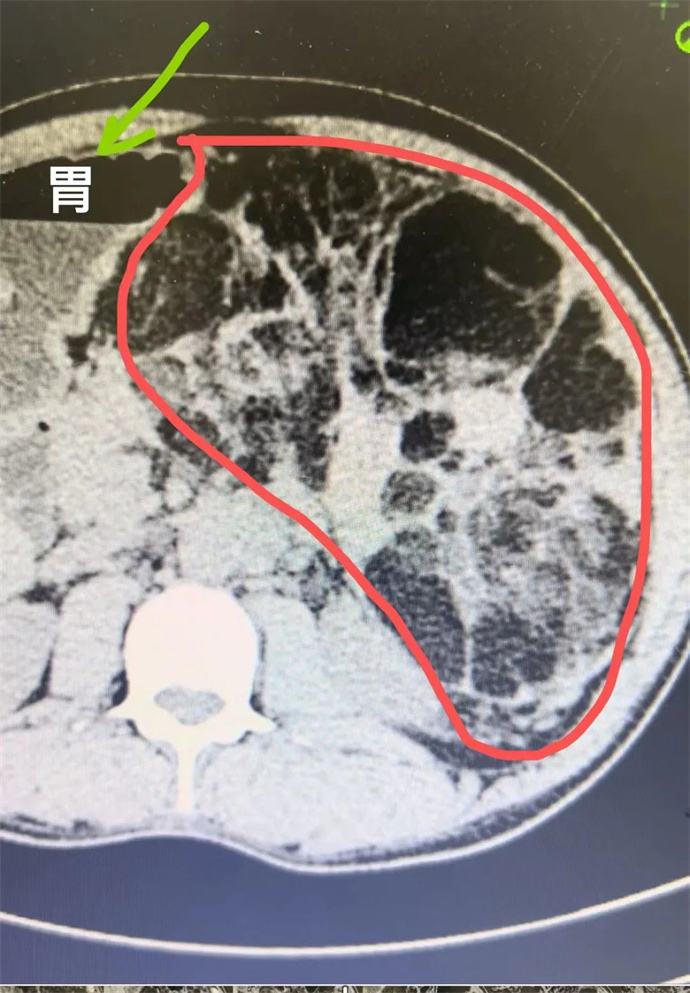

近日,我院泌尿外科會診一位四十多歲男性患者時發(fā)現(xiàn),該患者腹部有一巨大腫瘤,直徑近30cm,已將該患者胃、胰腺、脾臟及部分腸管擠壓移位,且腫瘤內(nèi)可見大量動靜脈畸形,存在極大的出血風險,一旦出血將危及患者生命,客觀告知患者及家屬相關病情后,患者及家屬憂心忡忡,基本的日?;顒佣夹挠形窇?,充分溝通后,轉(zhuǎn)入泌尿外科,擬行手術治療。

轉(zhuǎn)入泌尿外科后,強永春主任及專家組積極術前準備,仔細閱片,充分討論,明確此腫瘤來源為左側(cè)腎臟,多考慮為腎臟血管平滑肌脂肪瘤,俗稱“錯構瘤”。周莉護士長帶領護理組通過傾聽、解釋、鼓勵、提供支持、建立信任等來安撫患者的憂心忡忡,幫助他們更好地應對疾病??茖W、客觀的指導患者的術后康復。

錯構瘤屬于良性腫瘤,絕大多數(shù)錯構瘤患者沒有明顯的癥狀,一些比較大的錯構瘤,可能會出現(xiàn)局部壓迫癥狀或壓迫周圍臟器,出現(xiàn)相應的癥狀。腎錯構瘤最大的危害在于,體積較大的錯構瘤突然破裂時,患者會出現(xiàn)腰腹疼痛和血尿等癥狀,嚴重的大出血患者可以在腹部觸及到包塊,甚至有休克癥狀。因此當腫瘤直徑大于4cm時,一般會積極建議手術,減少自發(fā)破裂的風險。但該患者平素未行體檢,腫瘤已近30cm,因此貿(mào)然手術處理存在巨大的風險。

強永春主任帶領泌尿外科團隊積極協(xié)調(diào),提前預約腫瘤介入王忠主任,于術前行介入栓塞,減少術中出血風險;同時聯(lián)系輸血科提前術中備血;因腫瘤已侵及腎臟大部及腎臟血管,無法保留腎單位行腎部分切除,故先側(cè)臥位行后腹腔鏡下微創(chuàng)手術,游離并處理腎臟血管,確保切除時安全,再仰臥位行錯構瘤及腎臟切除;充分準備后,手術按預定方案如期進行,歷時6小時,成功拆除“定時炸彈”。目前患者已出院恢復了日常工作。